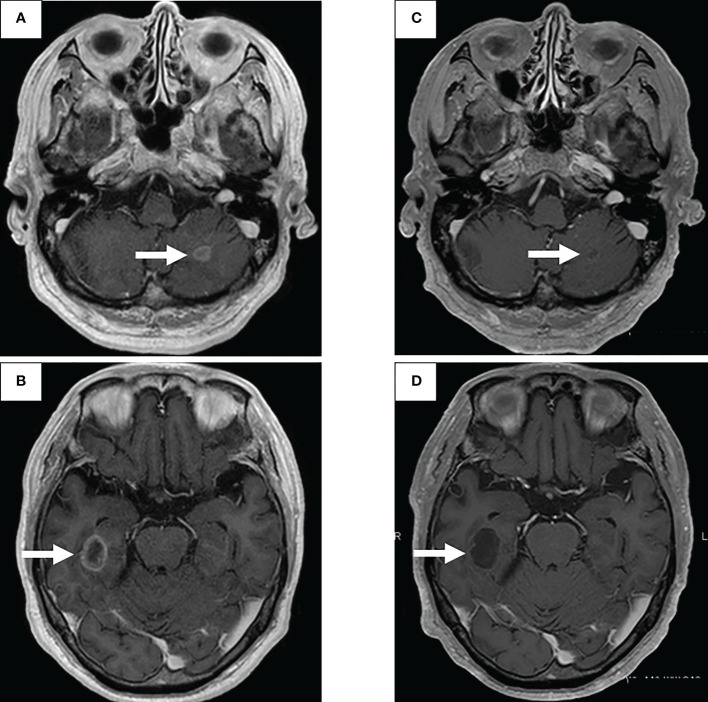

圖2:使用二線治療塞爾帕替尼的腦轉(zhuǎn)移療效

通過支氣管鏡對原發(fā)病灶進行再活檢,細胞學評估顯示V級腺癌,組織學評估證實了這一結(jié)果。腫瘤正確用藥850基因檢測確認患者為RET融合基因陽性,隨后于第二天給予240mg塞爾帕替尼。第13天的CT顯示與基線影像相比(圖1H),所有轉(zhuǎn)移病灶,包括腦轉(zhuǎn)移(圖2C、D),均有良好的全身反應。由于2級肝酶升高,繼續(xù)給予劑量減少的塞爾帕替尼(每天160mg)。使用高敏感度的下一代測序(NGS)面板系統(tǒng):肺癌緊湊面板,并使用細胞學刷液進行RNA檢測,證實了融合基因KIF5B外顯子15;RET外顯子12(K15RET12)。腫瘤正確藥基因解碼基因檢測還能夠從7年前的胸腔積液細胞塊的福爾馬林固定石蠟包埋(FFPE)標本中進一步確認RET(圖3A、B),這些標本在惡性細胞的形態(tài)學上與再活檢樣本相似,具有大核仁(圖3C、D)。從初始細胞塊樣本中收集到的RNA(1256ng)具有RNA整合數(shù)(RIN)值為4.8。單重PCR和NGS檢測均檢測到了K15RET12融合峰(圖3)。